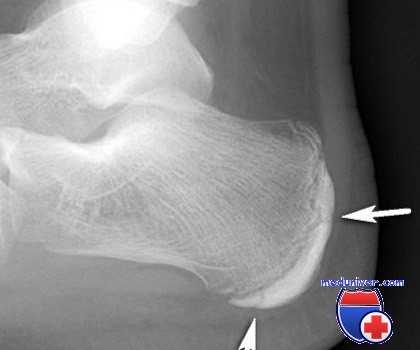

Пяточный эпифизит (болезнь Севера), наблюдаемое у детей, обычно мальчиков в возрасте 9—14 лет. Оно представляет собой вялотекущую воспалительную реакцию в заднем эпифизе пяточной кости, который, в отличие от остальной пяточной кости, имеет отдельный центр окостенения. Последний появляется у ребенка в возрасте 10 лет и сливается с пяточной костью в возрасте 15 лет.

Пациент жалуется на боль в заднем отделе пятки ниже места прикрепления ахиллова сухожилия, которая усиливается при стоянии на пальцах или беге. Начало постепенное, больной отмечает облегчение при расслаблении мышц голени при согнутом коленном суставе и стопе в положении эквинуса. Болезненность наиболее выражена по внутренней и наружной сторонам, где эпифизарная пластинка расположена подкожно.

Рентгенограммы в ранней стадии обычно неинформативны. Позже, однако, при сравнении со здоровой стороной можно определить фрагментацию эпифиза.

Заболевание — самокупирующееся, при рецидивах лечение симптоматическое до закрытия эпифизарной линии. Рекомендуется уменьшить натяжение ахиллова сухожилия, подложив под пятку прокладку толщиной 0,6 см для выведения стопы в положение эквинуса, а также назначить покой и обезболивающие средства. В тяжелых случаях может потребоваться иммобилизация стопы гипсовой повязкой в положении эквинуса.